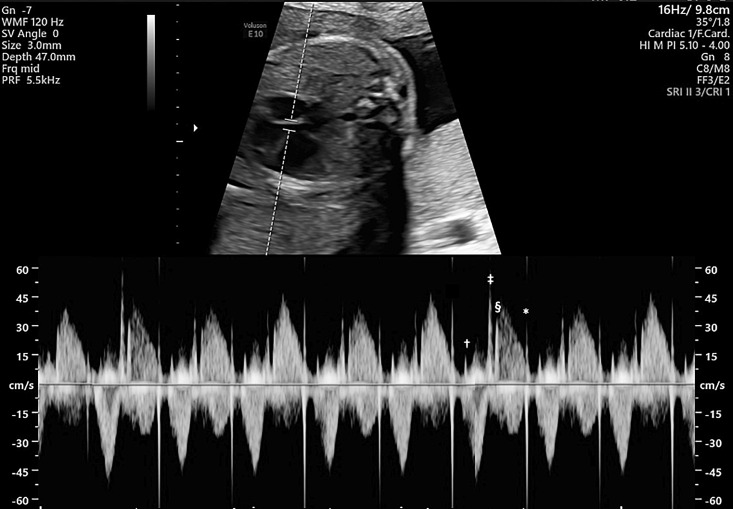

Introduction: The modified myocardial performance index (mod-MPI) is a noninvasive Doppler-derived metric used to evaluate fetal cardiac function. However, the reference ranges for mod-MPI in normal fetuses are not clearly defined, which limits the use of this technology in fetuses with potential cardiac compromise. Thus, we aimed to perform a systematic review and meta-analysis of published mod-MPI reference ranges across gestation.

Results: The search resulted in 618 unique citations, of which 583 did not meet inclusion criteria, leaving 35 abstracts selected for full-text review. Review of the references of these 35 articles identified another 5 studies of interest. Of the 40 articles reviewed, six met inclusion criteria. There was significant heterogeneity seen in the mod-MPI results reported. Mod-MPI increased as pregnancy progressed in all studies. The pooled mean mod-MPI at 11 weeks' gestation was 0.400 (95% CI 0.374-0.426) and increased to 0.585 (95% CI 0.533-0.637) at 41 weeks' gestation. The increase was linear in 5 of 6 studies, while in 1 study, the mod-MPI was stable until 27 weeks' gestation, and then increased throughout the third trimester. Despite all having trends increasing over pregnancy, there was no study in which all the weekly means fell within the pooled 95% CI.

Conclusion: While mod-MPI does increase over gestation, the true "reference ranges" for fetuses remain elusive. Future efforts to further optimize calculation of time intervals possibly via automation are desperately needed to allow for reproducibility of this potentially very useful tool to assess fetal cardiac function.